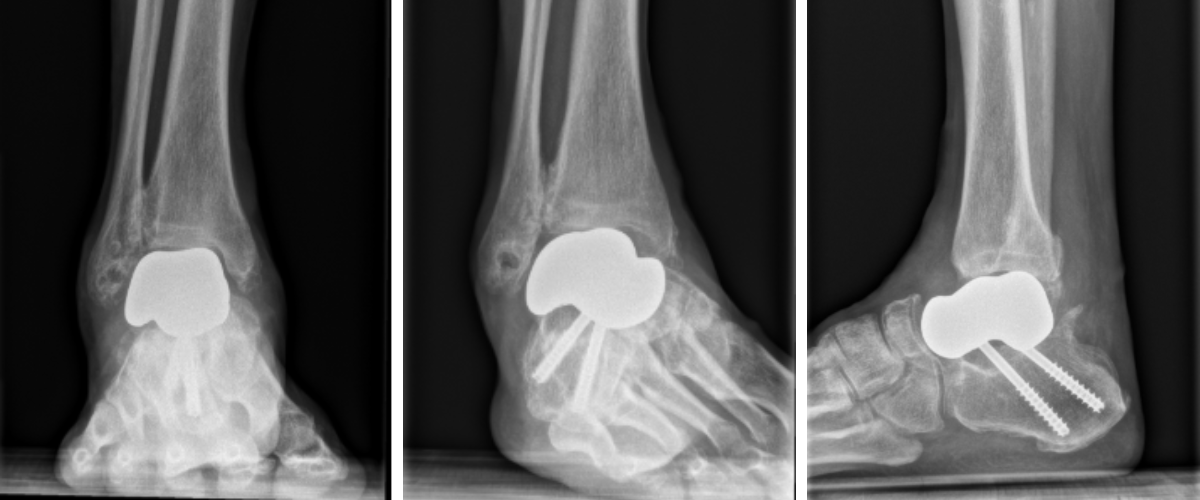

Postoperatively, radiographs and CT scans confirm proper alignment of the PEKK implant without any varus malalignment and adequate positioning (Figures 8 and 9). Postoperative ankle range of motion improved to 5 degrees dorsiflexion and 55 degrees plantarflexion. The patient remained non-weight-bearing for 3 weeks in a cast boot. He progressed to weight-bearing as tolerated in ankle stirrup brace with physical therapy. He returned to full activity and work by 6 months postoperative.

This revision restored ankle alignment and stability while avoiding the metallic debris–related complications seen with his prior implant, highlighting the utility of PEKK implants in complex revision total talus replacement cases.